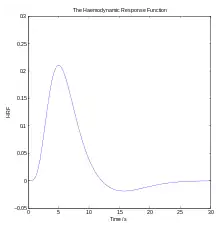

Functional magnetic resonance imaging

Functional magnetic resonance imaging (fMRI), is the medical imaging technique used to measure the haemodynamic response of the brain in relation to the neural activities.[12] It is one of the most commonly used devices to measure brain functions and is relatively inexpensive to perform in a clinical setting. The onset of neural activity leads to a systematic series of physiological changes in the local network of blood vessels that include changes in the cerebral blood volume per unit of brain tissue (CBV), changes in the rate of cerebral blood flow, and changes in the concentration of oxyhemoglobin and deoxyhemoglobin. There are different fMRI techniques that can pick up a functional signal corresponding to changes in each of the previously mentioned components of the haemodynamic response. The most common functional imaging signal is the blood-oxygen-level dependent signal (BOLD), which primarily corresponds to the concentration of deoxyhemoglobin.[13] The BOLD effect is based on the fact that when neuronal activity is increased in one part of the brain, there is also an increased amount of cerebral blood flow to that area which is the basis of haemodynamic response. This increase in blood flow produces an increase in the ratio of oxygenated hemoglobin relative to deoxygenated hemoglobin in that specific area. The difference in magnetic properties of oxygenated and deoxygenated hemoglobin is what allows fMRI imaging to produce an effective map of which neurons are active and which are not. In short, deoxygenated hemoglobin is paramagnetic while oxygenated hemoglobin is diamagnetic. Diamagnetic blood (oxyhemoglobin) interferes with the magnetic resonance (MR) signal less and this leads to an improved MR signal in that area of increased neuronal activity. However, Paramagnetic blood (deoxyhemoglobin) makes the local magnetic field inhomogenous. This has the effect of dephasing the signal emitted in this domain, causing destructive interference in the observed MR signal. Therefore, greater amounts of deoxyhemoglobin lead to less signal. Neuronal activity ultimately leads to an increase in local MR signaling corresponding to a decrease in the concentration of deoxyhemoglobin.[14]